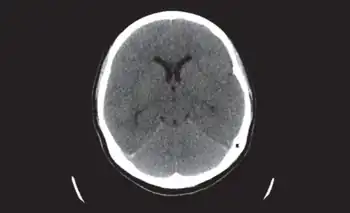

Clinical diagnosis includes evaluation for the presence of recurrent or recent herpes infection, fever, headache, altered mental status, convulsions, disturbance of consciousness, and focal signs. Testing of cerebrospinal fluid is usually performed.